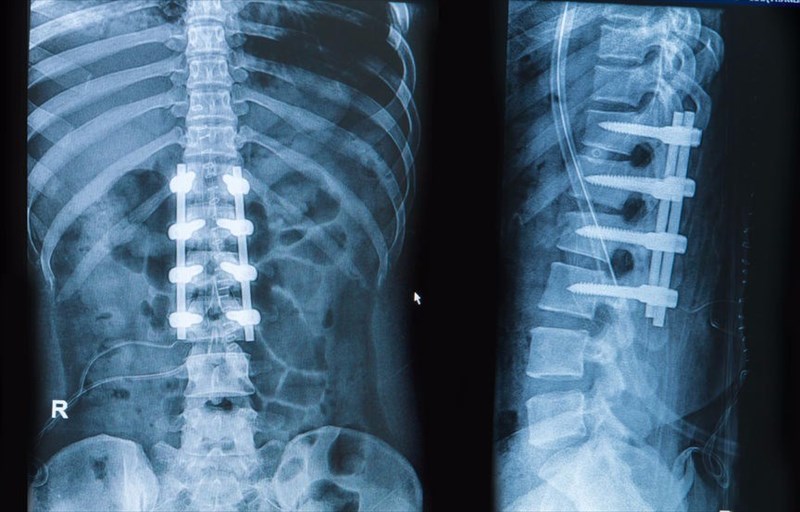

Surgical options for idiopathic scoliosis

Generally, there are three categories when it comes to surgery for scoliosis, these include:

• Fusion – This form of spinal surgery involves permanently fusing two or more vertebrae that are adjacent to each other so as to allow for them to grow together at a spinal joint and therefore, create a solid immobile

There are a number of modern approaches to this surgery which involve instrumentation such as screws, hooks, rods or wires that are placed within the spine to allow for a more efficient curvature correction to be achieved as well as a faster recovery time.

The different methods of spinal fusion include:

• Taking bone from the pelvis or from a bone bank and using this to create a bridge between adjacent vertebrae. This bone graft will assist new bone to grow.

• Using a metal implant to hold adjacent vertebrae together, this will then be removed when new bone has grown between them.

Spinal fusion is a major surgery and tends to last several hours. One of the main advantages of having spinal surgery is that it has a long-term record of efficacy and safety in the treatment of scoliosis. The drawback of spinal surgery is that a child is exposed to post-surgical risks such as infection and may lose mobility and have their twisting and bending capabilities limited. However, with today’s medical advances, surgeons are able to fuse fewer vertebrae together and thus greater mobility can be retained in comparison to surgeries conducted in the past.